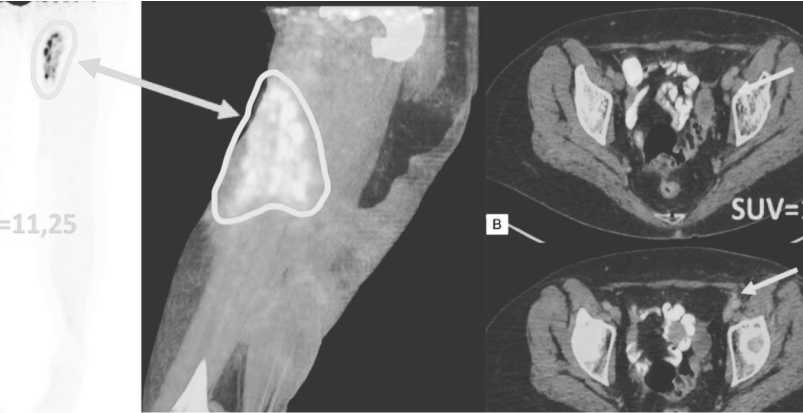

По результатам промежуточного контрольного ПЭТ/КТ исследования с 18F-ФДГ, был выявлен регресс большинства метаболический активных тазовых лимфатических лимфоузлов (до 3б по Deauville) и очагов, а также определялось уменьшение объема поражения кожи левого бедра (Рисунок 9). Полный местный ответ после проведенной лучевой терапии сохранялся в течение 2 лет.

Рисунок 9. ПЭТ/КТ с 18F-ФДГ после проведения конформной лучевой терапии. ПЭТ-изображение, фронтальная проекция (А), совмещенное ПЭТ/КТ–изображение, сагиттальная проекция в режиме многослойного изображения (Б), совмещенные ПЭТ/КТ–изображения, сагиттальные проекции (В, Г). В динамике определяется уменьшение зоны поражения кожи (обведено белым цветом и отмечено стрелкой),, а также снижение уровня накопления 18F-ФДГ в наружных подвздошных лимфоузлах слева до фоновых значений (отмечены белыми стрелками) / При сравнении с предыдущим ПЭТ/КТ исследованием определяется увеличение накопления 18F-ФДГ в зоне первичного очага, обусловленное постлучевыми воспалительными изменениями

Большинство пациентов с БПДКН получает системную химиотерапию. Для молодых больных без значимой коморбидности используют протоколы для лечения острых лейкозов, в том числе таргет-ную терапию. Так в работе Gilis L и соавт. проанализированы результаты лечения высокодозным метотрексатом и аспарагиназой 6 пациентов с БПДКН. У всех получен ответ на лечение [24]. В связи с гипе- рэкспрессией bcl-2 и эпигенетическим нарушением регуляции онкогенов патогенетически обосновано применение азацитидина и венетоклакса [25, 26]. Крупные исследования пока не завершены, однако клинические наблюдения показывают эффективность комбинаций венетоклакса с гипометилирующими препаратами [27, 28]. Представленная пациентка получала разнообразные протоколы лечения, однако стойкого ответа не достигнуто. С другой стороны, перед началом облучения по результатам ПЭТ обнаружена метаболическая активность преимущественно в тканях бедра, в абдоминальных и тазовых

лимфоузлах она была минимальна , а в селезёнке активности не было . Поэтому , вероятнее всего , ци тостатические препараты не проникали в крупные опухолевые очаги в коже и подкожной клетчатке , но были эффективны в остальных локусах .